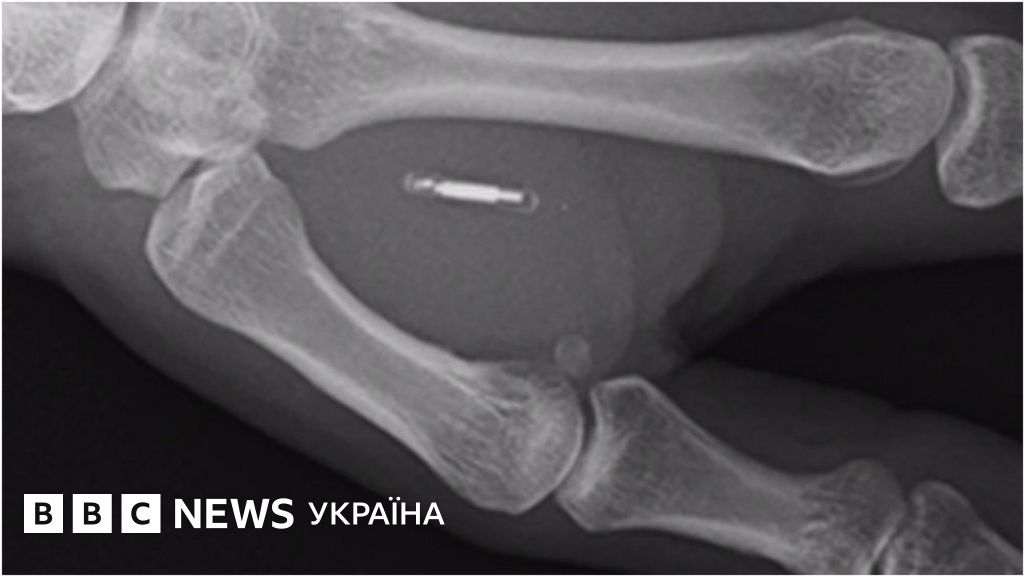

Чіп-імплант замість ключа для машини

Чи будуть люди в майбутньому розраховуватись за покупки або відчиняти двері не картками і ключами, а мікрочіпами у тілі.

Британський винахідник і бізнесмен Стівен Нортем вважає, що саме це - майбутнє.